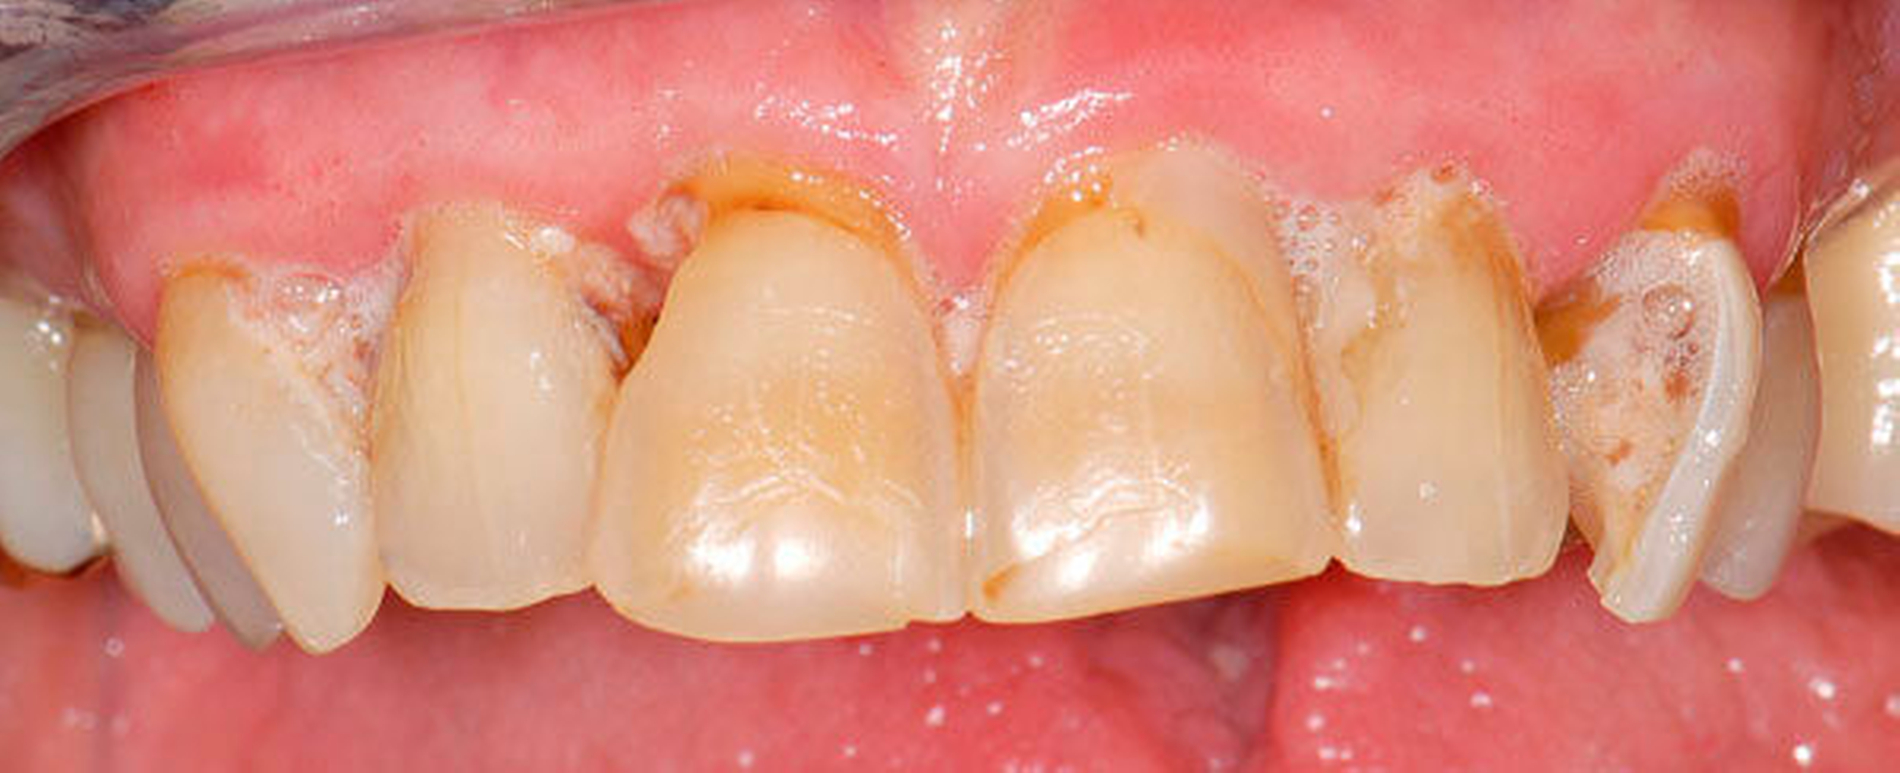

2. Management von Abrasionen, Attritionen und Erosionen

Fast alle bezahnten Senioren weisen deutliche Zeichen von altersentsprechenden Abrasionen, Attritionen und Erosionen auf. Bei langsamer Progression ist in restaurativer Hinsicht meist ein Zuwarten beziehungsweise eine individuelle Prävention indiziert. Bei schneller Progression empfiehlt sich hingegen eine rechtzeitige, teilweise von den Präparationsgrenzen unabhängige „Verschalung“ betroffener Areale mit direkt eingebrachtem Komposit unter Berücksichtigung der Antagonistensituation. Zuweilen müssen unter Abwägung der Vor- und Nachteile scharfe antagonistische Höckerspitzen vorsichtig subtraktiv abgerundet werden, wobei allerdings die Gefahr einer Dentinfreilegung besteht (Abbildung 2, Tabelle 2).

Abbildung 2: 66-jähriger Patient mit ausgeprägten, nicht kariesbedingten Hartsubstanzdefekten an Zahn 37 ohne klinische Symptome: Ob der Zahn jemals mit einer Restauration versorgt war, ist nicht bekannt. Der Patient wünscht an diesem Zahn keine Behandlung.